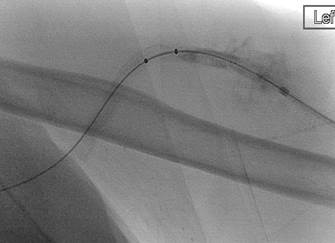

Thrombectomy of left brachial artery-axillary vein graft

Thrombosed AV graft with stenosis at venous anastomosis.

AngioJet DVX catheter in AV graft.